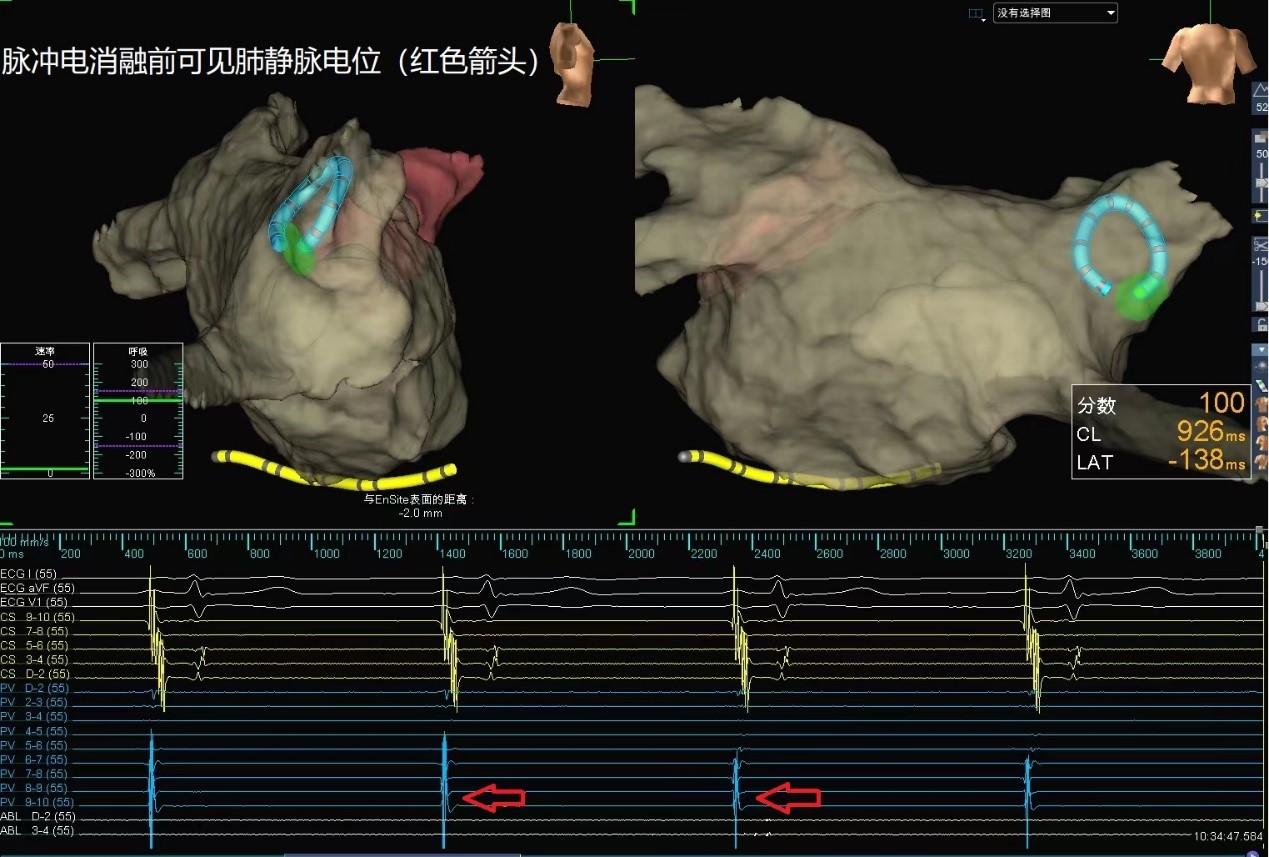

西北首例!心血管内科完成脉冲电消融房颤介入手术

心房颤动(房颤)是临床最常见的快速性心律失常,房颤发生时心房失去了正常有效的收缩功能,处于快速紊乱的颤动状态,会导致卒中、心衰等一系列严重并发症。目前我国房颤总患病人数超过1500万,并且随着年龄增长房颤的发生率不断增加,...